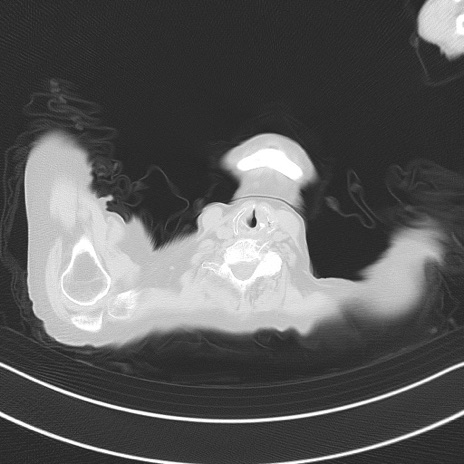

冠状断像

矢状断像